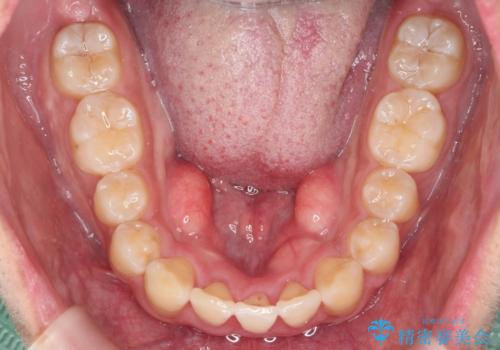

マウスピース矯正で前歯の角度、ガタガタをきれいに

- 突き出た前歯の角度、歯ブラシのしづらい前歯のがたつきの改善を希望され来院されました。

4本の小臼歯を抜きワイヤー矯正治療、下顎前歯を1本抜去しマウスピース治療のメリットデメリットを検討・相談し、より歯を抜く本数の少ないマウスピース矯正を行うこととなりました。

下顎の前歯は1本だけ抜去せざるをえませんでしたが、4本の小臼歯抜去とマルチブラケット矯正を回避することができ、治療結果・過程に満足いただくことができました。